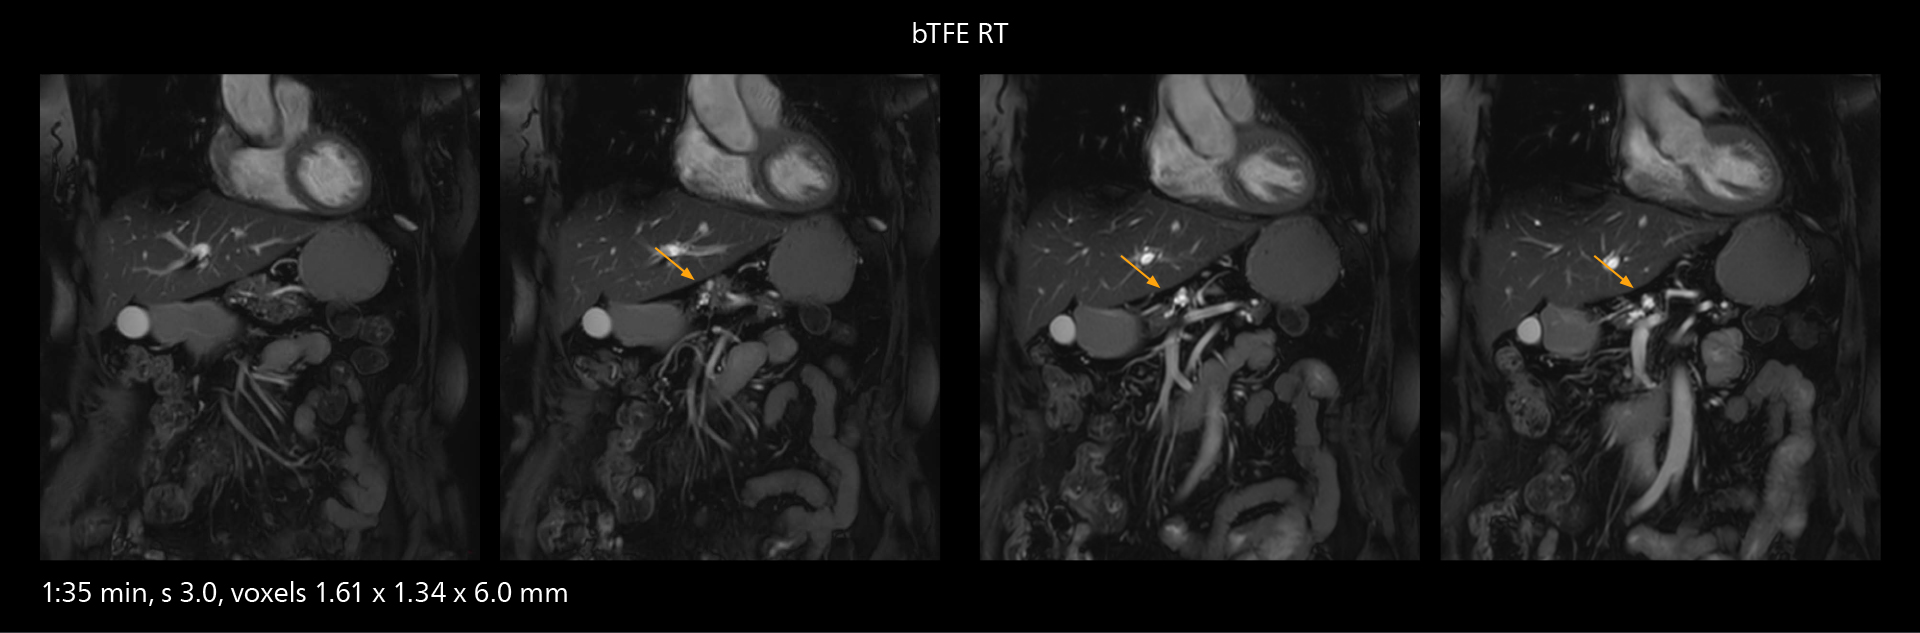

The value of the Elition X gradients is also evident in DWIBS studies. “The fact that we can consistently obtain distortion‐free DWIBS while reducing imaging time at three coronal stations is excellent,” Dr. Makuuchi says. “In these patients, it’s also important that the application of Compressed SENSE to T2‐weighted, STIR and mDIXON sequences has no impact on the examination time of whole‐body imaging. As a result of the increased speed and higher image quality we realize, DWIBS studies have now become routine examinations.”

Fast whole body DWIBS examination

With SmartPath to Elition X the team can obtain excellent quality DWIBS imaging and reduce imaging time. Other sequences also fit in the examination slot. This case shows left paravertebral neurogenic tumor and Th10 vertebral hemangiomas.